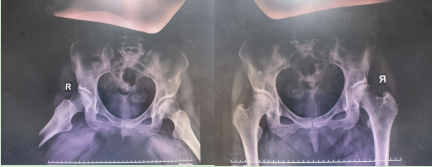

近日,骨关节一科收治的 58 岁患者,数月前出现髋关节疼痛,劳累时疼痛加重,休息时缓解,明确诊断前跑了很多家医院,多次进行系统性治疗未果,后来郑州中医骨伤病医院经明确诊治为股骨头缺血性坏死,髋关节髋臼发育不良。

检查结果显示,该患者左侧髋臼浅,受劳累及日常关节磨损继发性股骨头缺血性坏死,医生和护士便向患者讲解了髋关节发育不良所能引起的髋关节疾病,包括但并不限于股骨头缺血性坏死。